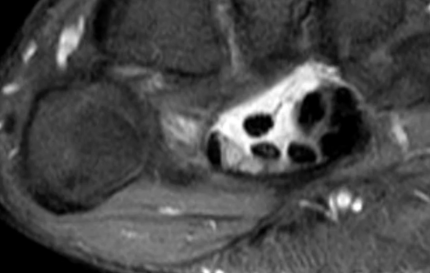

Tenosynovite de la jeune maman (de Quervain)

- Ténosynovite du premier compartiment

- Mères qui portent leur enfant ++

- Inflammation des tendons au niveau de la styloide radiale